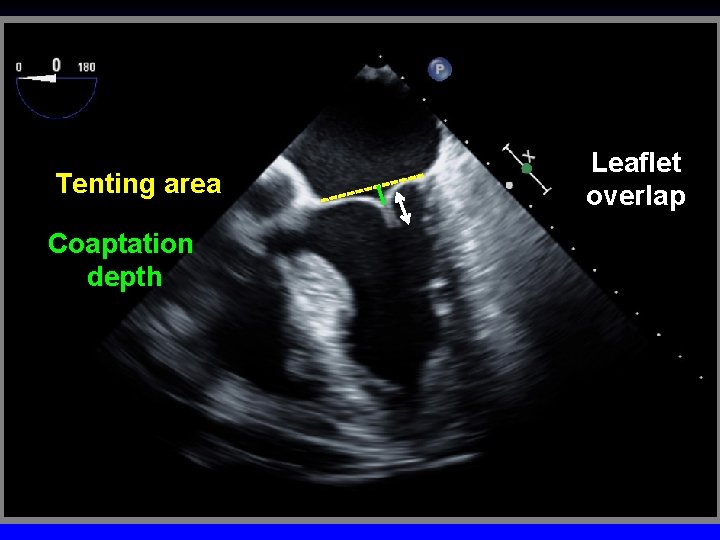

Inter-commissural distance Aorta Septo-Lateral distance Tent Vol Coapt Displ Tenting Height Coaptation length

Tenting area Coaptation depth Leaflet overlap

Ischemic Mitral Regurgitation C B A D Mitral leaflets are tented apically Mitral annulus is enlarged (A-B = 45 mm) Mitral coaptation depth is increased (C-D = 13 mm)

Eligibility Criteria for Mitra. Clip Functional MR Degenerative MR Coaptation Length ≥ 2 mm Flail Gap <10 mm Coaptation Depth <11 mm Flail Width < 15 mm adapted from Cavalcante JACC CV Imaging 2012; 5: 733 -746